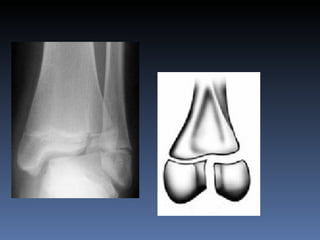

Fractura Intra-articular  involucra la superficie articular de la articulacion subyacente